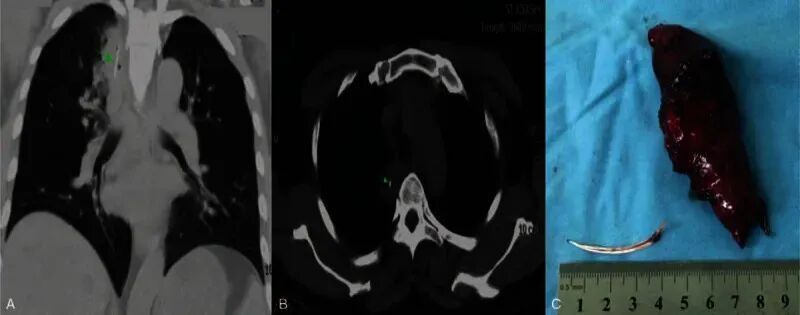

在极少数情况下,鱼刺甚至可能因为反复的错误尝试穿透食管进入胸腔或肺部。一例病例报道显示,患者在误吞鱼刺后出现肺部脓肿,最终需要胸腔镜手术取出异物[5]

图片

A图和B图为一根长4厘米的鱼刺嵌在右肺上叶的脓肿中。C图为鱼刺和肺脓肿的合影。图源:参考资料[5]

这类情况虽然罕见,却清楚地说明了一点:错误处理,会把一个原本可控的问题,推向高风险路径